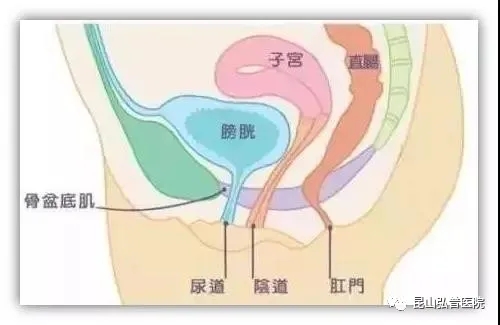

盆底肌是指封闭骨盆底的这一部分肌肉群。它像一张吊网一样托着我们的尿道、膀胱、直肠、阴道、子宫、前列腺等脏器。使这些脏器维持其正常的位置,良好的行使其功能。

女性盆底肌群大致分为三个部分:肛门附近的括约肌、阴道附近肌肉群以及控制尿道的肌肉群。

控制排尿、排便

一旦盆底肌群功能异常,弹性变差,就会造成漏尿、便秘,甚至大小便失禁、盆底的子宫等脏器脱垂,性功能降低等情况,影响生活质量。